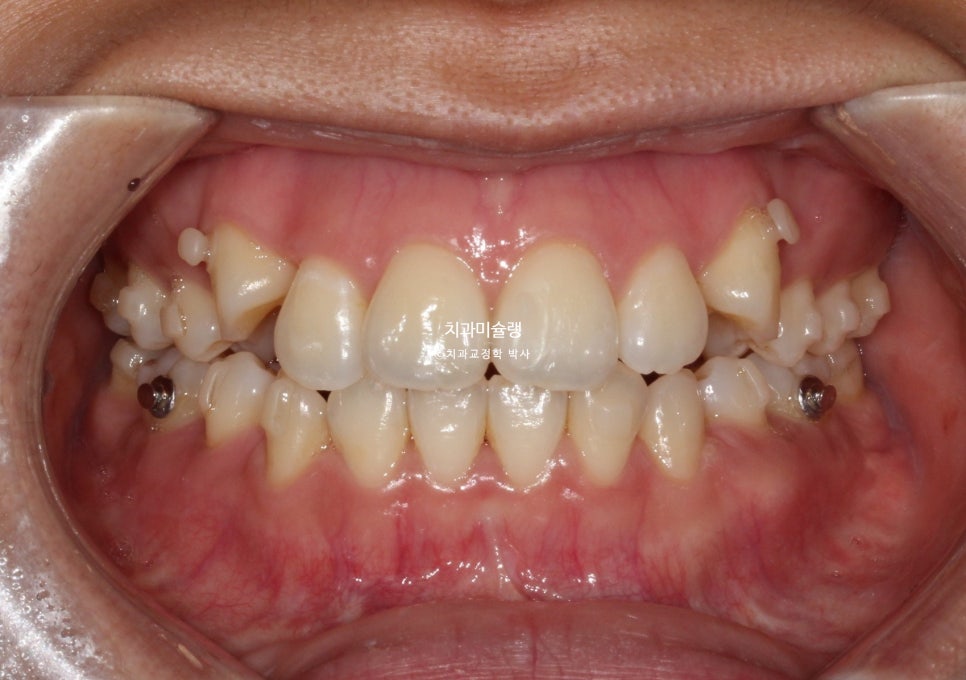

치료 진행 과정

치료 중 워낙 위치가 높았던 송곳니가 잘 맞지 않아 고무줄을 끼면서 진행했고

치료 시작 1년째 – 첫 번째 재제작

치료시작 1년째, 송곳니가 발치공간으로 대부분 들어온 이후 51번 장치에서 일찍 재제작을 했습니다.

추가장치 갯수는 27개가 나왔으며 2025년 2월까지 5개월간 열심히 낀 후 모습입니다.

중심선은 잘 맞으며 송곳니는 제자리로 잘 내려왔죠. 개방교합도 완벽히 개선되었습니다.

어금니 교합은 이미 좋습니다.

두 번째 재제작

약간의 교합 개선과 발치공간이 미세하게 남아 두번째 재제작에 들어갔습니다.

그렇게 추가장치를 끼며 중간에 무사히 출산도 하시고, 23개 장치를 다 낀후 내원시 모습입니다.

중심선 교합은 좋고 발치공간도 타이트 하게 마무리 되었습니다.